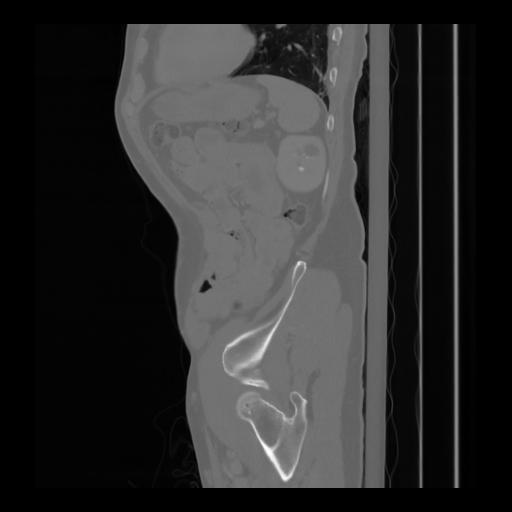

36 CUERPO,CE,Sagittal,3.000,CUERPO,Sagittal,